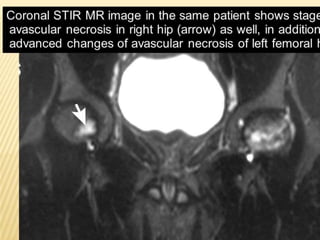

MRI

 An important feature in differentiating bone infarct from other

medullary lesions is that the central signal usually remains that of

normal marrow. The marrow is not replaced.

 T1

 serpiginous peripheral low signal due to granulation tissue and to

lesser extent sclerosis

 peripheral rim may enhance post gadolinium

 central signal usually that of marrow

 T2

 acute infarct may show ill-defined non-specific area of high

signal

 double-line sign: hyperintense inner ring of granulation tissue

and a hypointense outer ring of sclerosis

 absence of double-line sign does not exclude bone infarct

MRI  An importantfeature in differentiating bone infarct from other medullary lesions is that the central signal usually remains that of normal marrow. The marrow is not replaced.  T1  serpiginous peripheral low signal due to granulation tissue and to lesser extent sclerosis  peripheral rim may enhance post gadolinium  central signal usually that of marrow  T2  acute infarct may show ill-defined non-specific area of high signal  double-line sign: hyperintense inner ring of granulation tissue and a hypointense outer ring of sclerosis  absence of double-line sign does not exclude bone infarct  central signal usually that of marrow